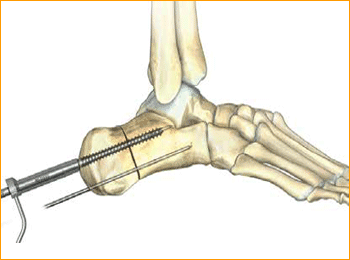

9. SCREW INSERTION

Cannulated Screws are placed. Placement is confirmed by lateral and axial fluoroscopy views in the operating room.

Caution: The marking on the driver shows when the screw is approximately flush with the end of the soft tissue protector; assure that the soft tissue protector is touching bone to accurately determine screw depth. Verify final screw position with fluoroscopy.

10. ADDITIONAL SCREW PLACEMENT

Repeat steps 5–9 for each additional screw placement. The operative limb is placed into a bulky compression dressing. A splint is also placed. Patients are made non-weight-bearing in a cast, boot, or splint for 6 weeks after surgery.